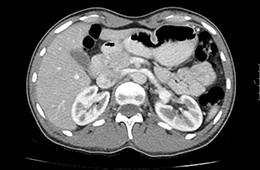

Bei der CT handelt es sich um ein röntgendiagnostisches computergesteuertes Verfahren. Bei der Untersuchung liegt der Patient auf einer beweglichen Liege, die innerhalb weniger Sekunden durch eine kurze Röhre fährt. In dieser wird er von einem Röntgenstrahler umkreist, wobei schichtweise Aufnahmen aus vielen Richtungen entstehen. Aus diesen ergibt sich bei modernen Multislice-Scannern ein dreidimensionaler Datensatz, der anschließend an einem Hochleistungscomputer durch den Radiologen ausgewertet wird.

Die CT wird bei diversen Erkrankungen zur Klärung von Organveränderungen, Blutungen und Flüssigkeitsansammlungen sowie auch bei Tumorverdacht durchgeführt. Auch Verengungen und Verkalkungen in den hirnversorgenden Gefässen, der Körperschlagader, den Herzkranzgefäßen oder Tumoren im Darm können heute mittels CT nachgewiesen werden. Hinsichtlich bestimmter Erkrankungen der Lunge und des Bauchraumes und hinsichtlich der Untersuchung von schwerkranken oder beatmeten Patienten gibt es derzeit häufig keine strahlungsfreien Alternativen. Die CT ist daher in vielen Fällen eine unverzichtbare radiologische Methode zur Erfassung krankhafter Veränderungen im menschlichen Körper, deren Nutzen das Strahlenrisiko bei weitem übertrifft.

Bei Untersuchungen des Bauchraumes wird häufig verdünntes Kontrastmittel oral verabreicht, das in zwei Bechern über etwa 45-60 Minuten getrunken wird.